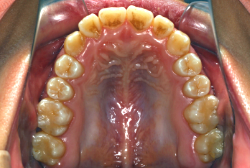

「上の前歯の凸凹」という主訴で来院したケースです。確かに上の左右二番目の歯が内側に引っ込んでいて、凸凹が目立つ状態です。歯並びの凸凹を矯正学では 叢生(そうせい)と言いまして、確かにご本人的にはそこが気になるのですが、矯正学的には前歯の前突の方がより問題となるケースです。

初診時の写真をご覧いただくと、何となく前歯が前傾しているのが感じられると思うのですが、よく見ると上の歯だけでなく、下の前歯も前傾しているのがわかります。このように上の前歯も下の前歯も両方外向きになっている症状のことを、「上下顎前突」と言います。こういうケースの場合は上下左右の小臼歯を抜く(つまり4本抜歯する)ことで配列の中に隙間を作り、その隙間を利用して配列を揃えるだけでなく、 前歯を内側に入れていく治療をします。

治療前後の口元の変化です。前歯の角度が大きく変わりました。治療前は外向きの前歯に押されて、口元がふくらみすぎの状態でした。黄色の線は鼻の頂上と顎の先端を結んだ線で、審美線と言います。審美線と唇はあまり接触しない方が良いと考えられています。矢印の部分がかなりラインオーバーしています。治療後はよりスマートで美しい横顔になりました。このように歯並びを直すと、唇の表情ひいてはお顔全体の表情にも良い変化が生まれます。